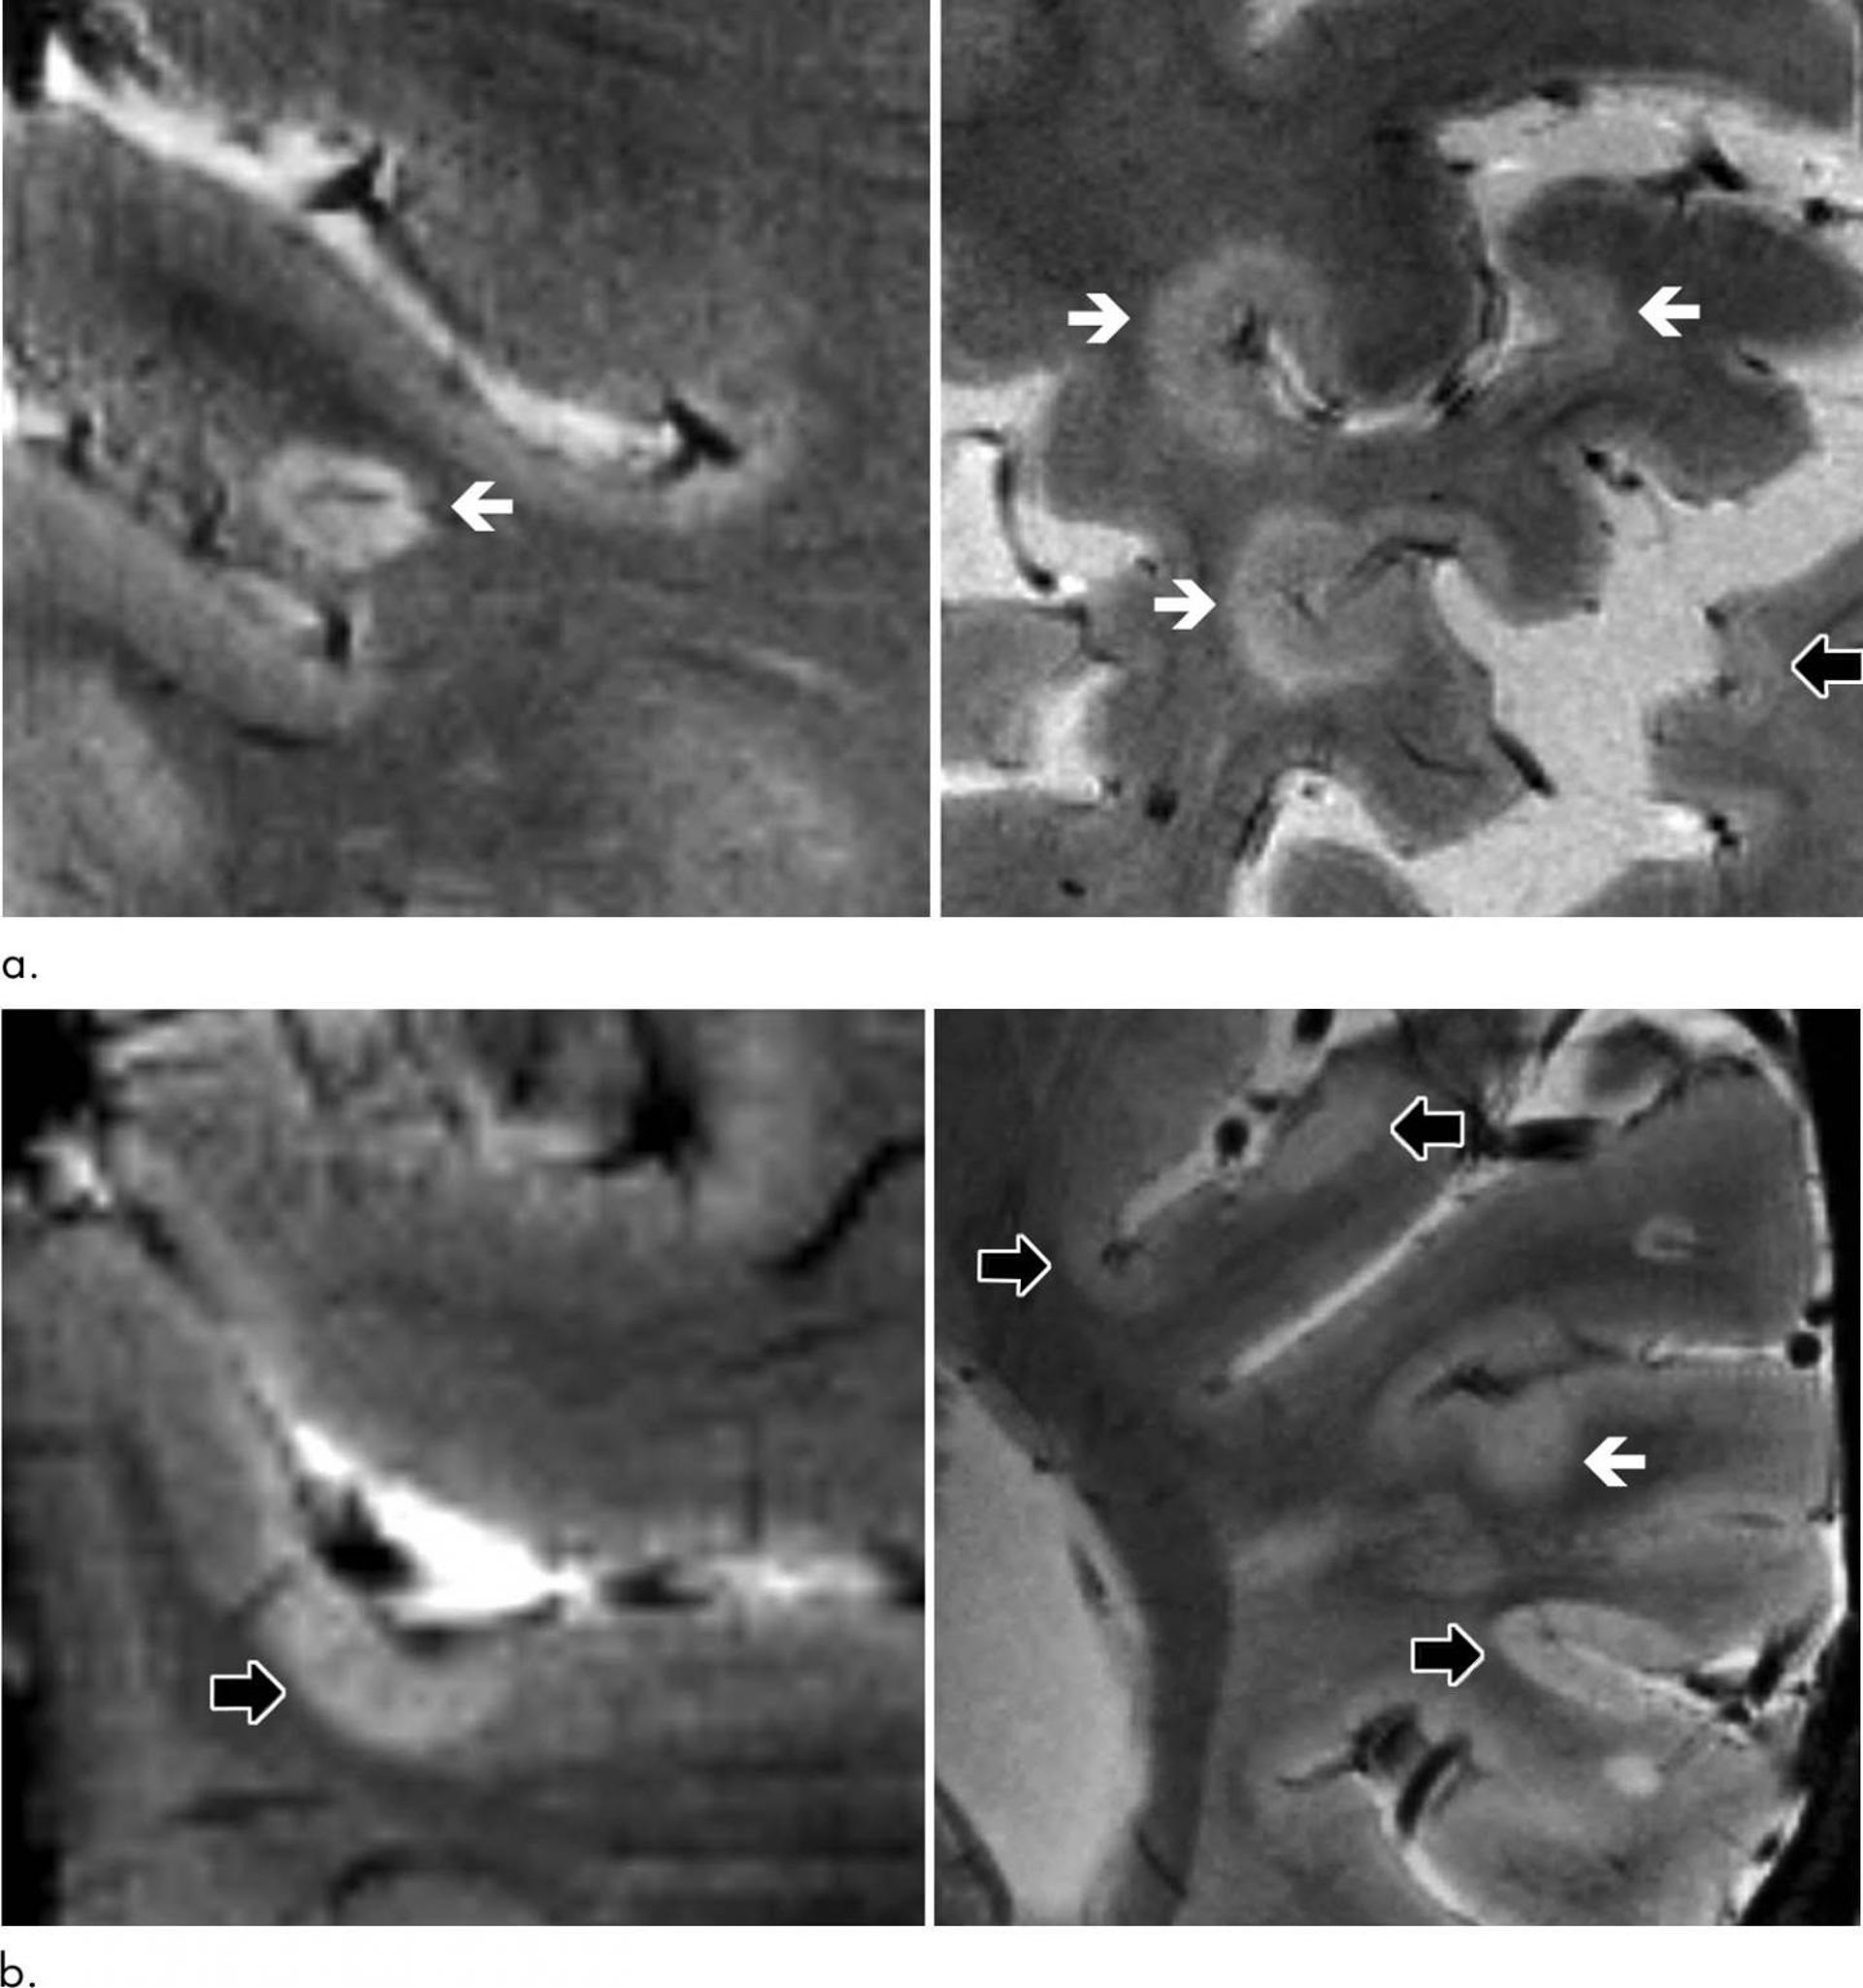

Veinticinco de los pacientes con EM, o el 80 por ciento, desarrollaron nuevas lesiones corticales, y la resonancia magnética 7T las detectó con más frecuencia en comparación con estudios previos en la RM de campo bajo de fuerza. En promedio, el número de lesiones que se desarrollaron en la región cortical fue más del doble del número que se produjo en la sustancia blanca del cerebro.

El volumen total de lesiones corticales fue un predictor de discapacidad neurológica en la evaluación inicial y de seguimiento. Los escáneres cerebrales 7T mostraron que las lesiones corticales tendían a acumularse en las marcas de la superficie del cerebro llamados surcos.

"Demostramos que los surcos corticales son las regiones donde se desarrolla la mayoría de estas lesiones --dice el doctor Mainero--. También descubrimos que estas lesiones pueden predecir la progresión de la discapacidad más que las lesiones de la materia blanca, que son las lesiones típicas de la EM que hemos estado estudiando durante años".

Aunque las razones de la acumulación de lesiones en los surcos no se conocen de manera definitiva, los investigadores señalan que es probable que el flujo de líquido cefalorraquídeo (el líquido que rodea el cerebro y la columna vertebral) esté restringido allí. El flujo restringido puede hacer que los surcos sean más vulnerables a las respuestas inflamatorias.